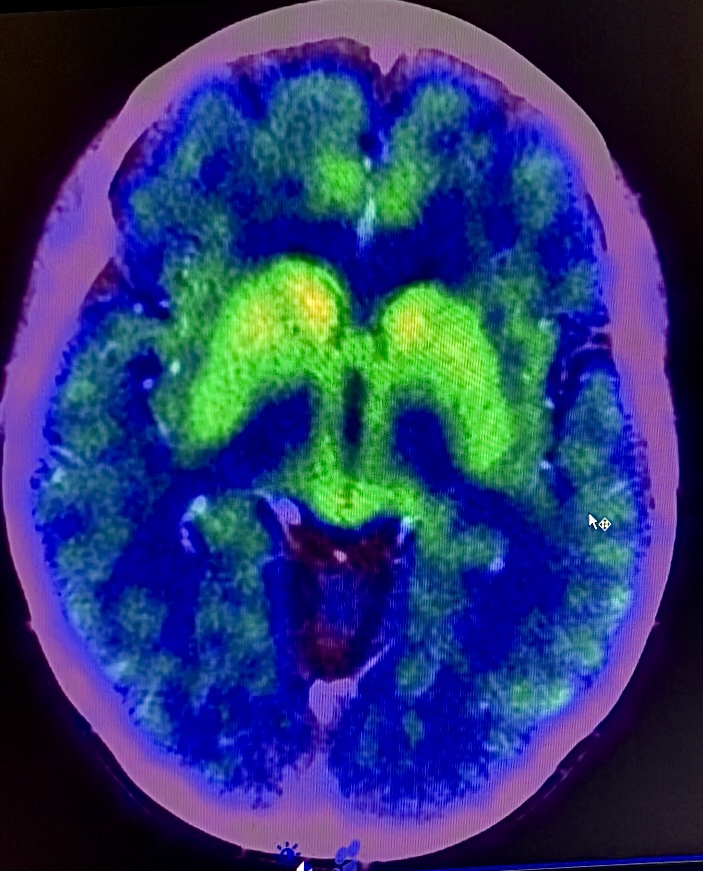

Results: Genetic testing of 61 genes revealed two heterozygous mutations of uncertain significance (c.2233C>T p.His745Tyr and c.8341T>A p.Ser2781Thr) in the VPS13A gene. Magnetic Resonance Imaging (MRI), with absence of the “swallow tail” sign in the left cerebral peduncle. PET-F-Dopa, uptake consistent with presynaptic alteration of the nigrostriatal system and the LD test showed an improvement of >83% within 1 hour after taking medication.

Image 1. B (PET-F-Dopa 22.02.24).